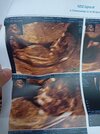

Mam do Was pytanie odnośnie liczenia tygodni/dni ciąży. Do piątkowego usg liczyłam 11+1 (wg owulacji i poprzednich usg), a maluszek nadrobił 2 dni i był długi na 11+3. Dzisiaj utrzymał tempo wzrostu względem poprzedniego usg, czyli crl odpowiadało 12+0. Z tego, co powiedziała dzisiaj ginekolog, ten termin się już nie zmieni. Czy liczyłybyście od teraz 12+0 wg usg (a w zasadzie dwóch ostatnich), czy 11+5, czyli tak jak z owulacji? Z OM od początku nie liczyłam, bo znam dokładną datę owu. Maluch ma 5,5cm.